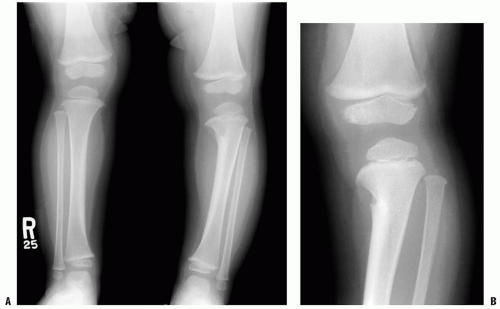

Children represent a distinctive group in orthopaedics. Management of paediatric disorders present unique challenge and require special skills for their management. Summit Orthopaedic Hospital routinely performs paediatric procedures such as

• 1. Treatment of congenital deformtiies such CTEV foot, DDH etc.

• 2. SCFE

• 3. Deformity ( congenital and posttraumatic) correction.